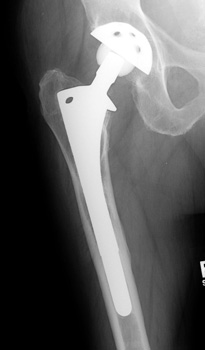

Total Hip Arthroplasty

• Used in patients with arthritic conditions that involve the acetabulum and the femoral head

• Types

• Non cemented

• Porous coated

• Press fit

• Hybrid (only femoral component cemented)

• Cemented

Non Cemented